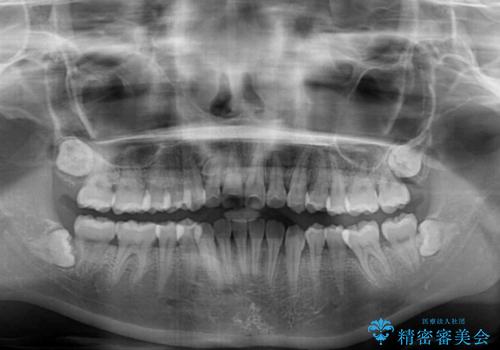

- 上顎歯列と下顎前歯の叢生を気にして来院された患者様です。

上顎からワイヤー矯正を開始し、終了間際から下顎前歯の叢生解消するよう計画しました。

部分矯正でしたが、咬み合わせに違和感が出ることなく気になる部分を改善させることができました。